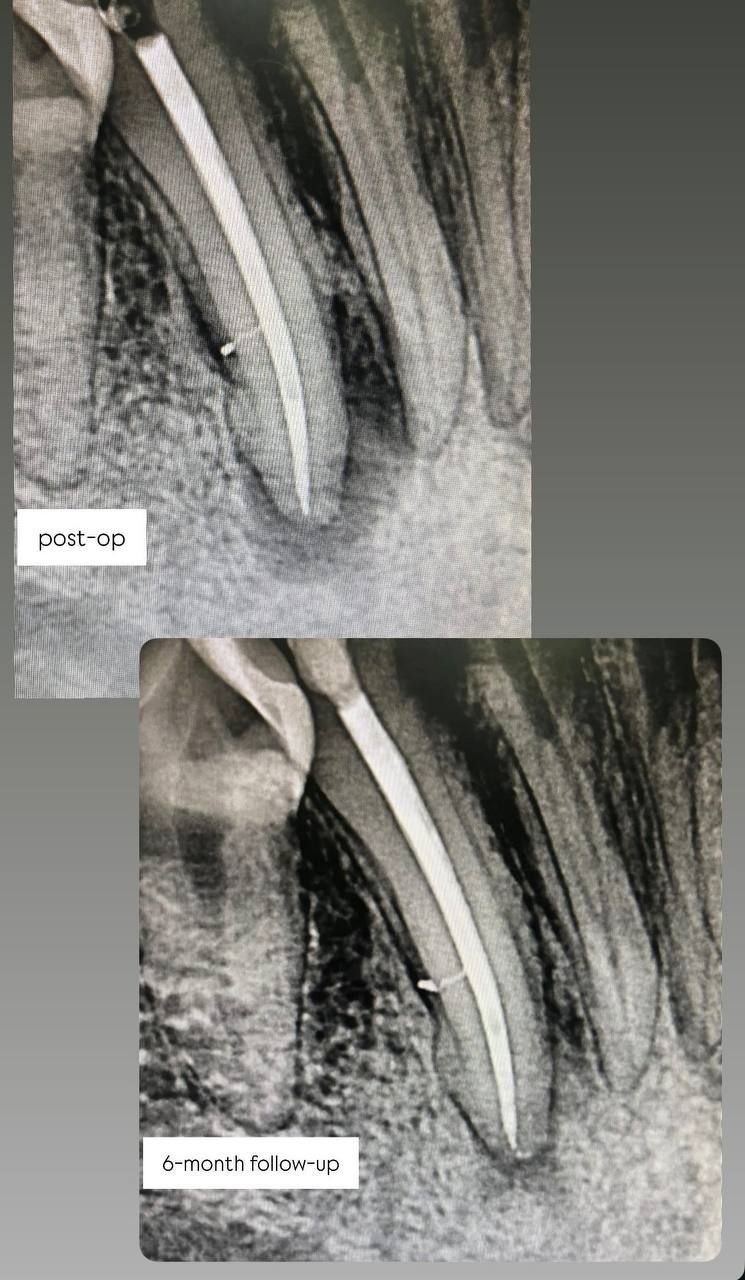

Jestem lekarzem dentystą zajmującym się stomatologią zachowawczą oraz leczeniem kanałowym pod mikroskopem (endodoncja mikroskopowa). W swojej pracy stawiam na kompleksowe podejście do zdrowia jamy ustnej – dokładną diagnostykę, skuteczne leczenie oraz profilaktykę.

Specjalizuję się w leczeniu próchnicy, odbudowie zębów oraz leczeniu kanałowym, w tym leczeniu kanałowym pod mikroskopem, które pozwala na bardzo precyzyjne oczyszczenie i opracowanie kanałów korzeniowych. Dzięki zastosowaniu mikroskopu możliwe jest skuteczne leczenie nawet bardziej skomplikowanych przypadków oraz powtórne leczenie kanałowe (reendo).